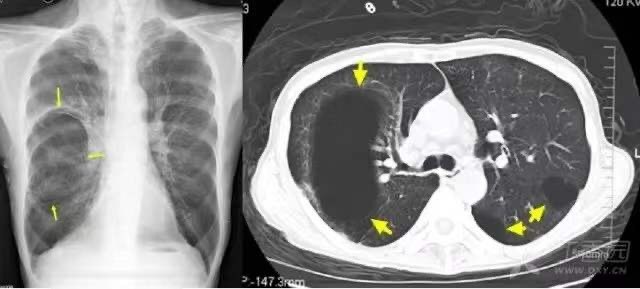

1.4. 肺渗出性病变:支气管肺炎

1.5. 肺渗出性病变(实变): 大叶性肺炎

平片示右肺上叶密实,下缘清晰(箭示);CT 所见右肺上叶实变,可见空气支气管征(箭示,提示叶、段及亚段支气管通畅)。

1.6. 肺渗出(浸润)性病变:浸润型肺结核

平片、CT 所见双肺散布片絮状影,并可见树芽征